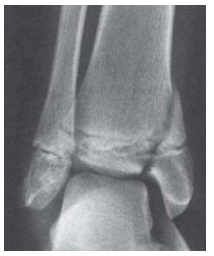

Uma paciente idosa apresentou episódio de vertigem rotatória e caiu com o punho fletido. No exame físico, apresenta deformidade importante de punho, edema e dor limitante.

Com base nesse caso clínico e nas imagens de radiografia apresentadas, é correto afirmar que se trata de uma fratura de